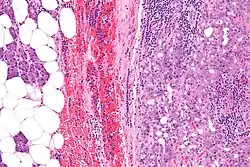

| Micrograph of an acinic cell carcinoma (right of image) and acinar glands (parotid gland - left of image). H&E stain. | |

Histopathologic features

Basophilic, bland cells similar to acinar cells. Growth pattern: solid - acinar cells, microcytic - small cystic spaces mucinous or eosinophilic, papillary-cystic - large cystic lined by epithelium, follicular - similar to thyroid tissue.

These tumors, which resemble serous acinar cells, vary in their behavior from locally aggressive to blatantly malignant.